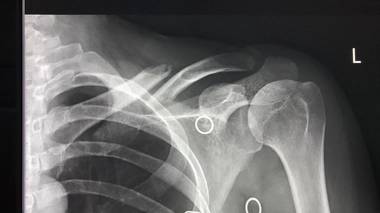

Hanche et fracture du col du fémur

La hanche est une articulation complexe, indispensable à la marche. Avec un point faible : le col du fémur. Cette fracture immobilise 50 000 Français chaque année, elle nécessite souvent la pose d’une prothèse de hanche.